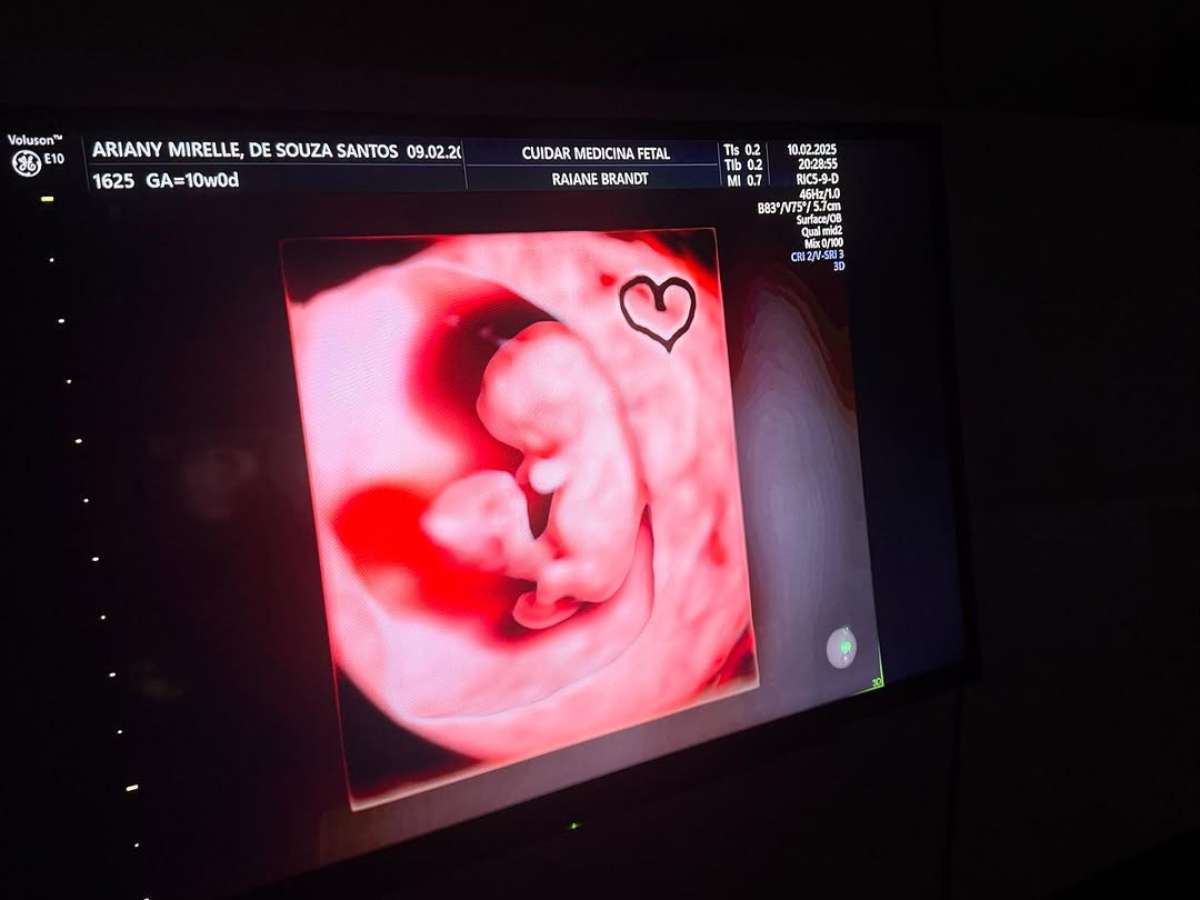

João Gomes e Ary Mirelle divulgam ultrassom do segundo filho

João Gomes e esposa Ary Mirelle postaram fotos do ultrassom de Joaquim, o segundo filho que o casal está esperando

O cantor João Gomes, de 22 anos, e sua esposa Ary Mirelle, de 23 anos, estão esperando o segundo filho, e já compartilharam o ultrassom do bebê. O exame acontece esta semana, e eles postaram em suas redes sociais os primeiros registros de Joaquim, nome escolhido para o pequeno.

"Dia de visitar Joaquim…", escreveu o casal, que postou as imagens juntos no Instagram. Enquanto isso, nos comentários da publicação, Ary escreveu: "Quinzinho da mãe e do pai dele, nós te amamos tanto". O anúncio da gravidez do segundo filho veio no dia 14 de fevereiro. João Gomes já é pai de Jorge, um menino de um ano. Agora, esperam um irmãozinho para ele.

Foto: Reprodução/Instagram / Famosos e Celebridades